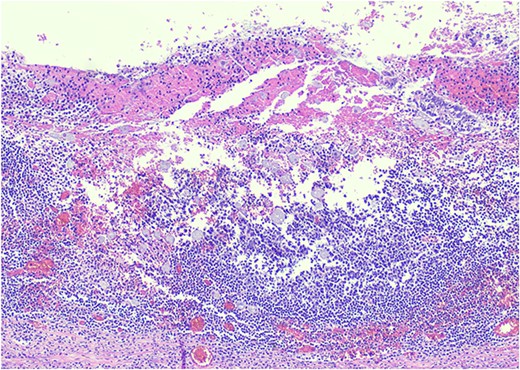

Pathology resulted on post-operative day three showing an inflamed appendix, 1.4 cm in diameter, with an exudative-filled lumen. On microscopic stains, there was evidence of acute appendicitis with frequent scattered unicellular organisms within areas of ulcerated appendiceal mucosa and submucosa (Figs 6 and 7). These cellular forms have round cell membranes, single prominent round eosinophilic nuclei and foamy cytoplasm (Fig. 5). Occasional forms show evidence of erythrophagocytosis (Fig. 3). Forms were also highlighted by trichrome and PAS special stains (block A1) and were negative for CD68 (a marker of macrophages; block A1) (Figs 2–4). These morphologic features are most consistent with E. histolytica, which is a pathogenic parasite in the lower GI tract, and likely the causative agent for acute appendicitis in this case.

H&E 200X—unicellular parasites within submucosal tissue with inflammation.